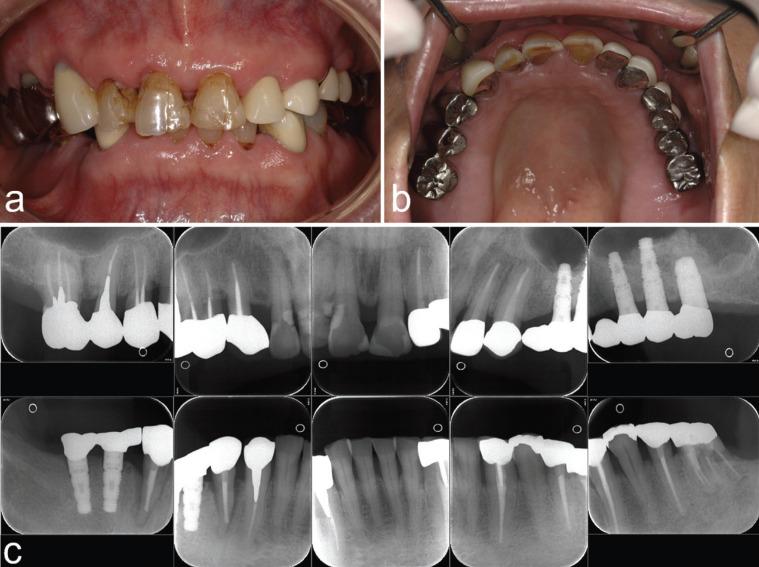

This report presents a 20-year follow-up of a unique case involving a 46-year-old man who underwent sinus augmentation using autogenous demineralized dentin matrix (DDM) derived from non-functional teeth. Two extracted molars were crashed into granules, and then demineralized, freeze-dried, and stored at -80° for approximately one year. The stocked DDM granules were grafted into the sinus along with platelet-rich plasma, without the use of any membrane. Radiographic evidence at 1 month after the graft demonstrated successful harmonization of the augmented tissues with the atrophic maxilla, as shown by the increase in radiopaque dots. Computed tomography scans taken 5 months post-procedure revealed clear sinuses devoid of inflammation, significant bone formation, and a smooth buccal side outline. Bone biopsies at 5 months were carried out from the implant sites, and three fixtures were placed into the augmented bone. The biopsy tissues confirmed the presence of continuous trabecular bone linked with DDM, with new bone formation observed on it. A comparison of the dental X-ray images taken in 2009 and those captured in 2021 indicated minimal change in the outline of the new bone formed near the fixture-necks through the DDM graft and successful placement of dental implants was achieved. Based on this long-term case study, it is suggested that autogenous DDM graft could serve as a minimally invasive alternative for sinus bone augmentation without invasive bone harvesting and the associated morbidities. Atrophic maxilla, autograft, bone, dentin, demineralized dentin matrix, sinus augmentation, teeth.

本报告介绍了一例独特病例的20年随访情况,该病例为一名46岁男性,他使用源自无功能牙齿的自体脱矿牙本质基质(DDM)进行了鼻窦增高术。将两颗拔除的磨牙粉碎成颗粒,然后进行脱矿、冻干,并在-80°下储存约一年。将储存的DDM颗粒与富血小板血浆一起植入鼻窦,未使用任何膜。移植后1个月的影像学证据显示,增强组织与萎缩性上颌骨成功融合,表现为不透射线的小点增加。术后5个月进行的计算机断层扫描显示鼻窦清晰,无炎症,有明显的骨形成,颊侧轮廓光滑。在5个月时从种植部位进行骨活检,并将三个种植体植入增强骨中。活检组织证实存在与DDM相连的连续小梁骨,并在其上观察到新骨形成。对2009年和2021年拍摄的牙科X线图像进行比较,结果表明通过DDM移植在种植体颈部附近形成的新骨轮廓变化最小,并且成功植入了牙种植体。基于这一长期病例研究,提示自体DDM移植可作为鼻窦骨增高的微创替代方法,无需进行侵入性骨采集及相关并发症。萎缩性上颌骨、自体移植、骨、牙本质、脱矿牙本质基质、鼻窦增高、牙齿。